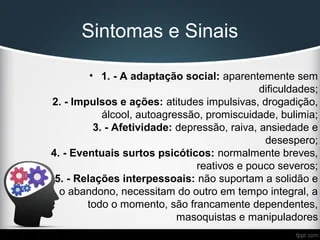

Transtorno de Personalidade Borderline21 março 2025

Transtorno de Personalidade Borderline21 março 2025 -